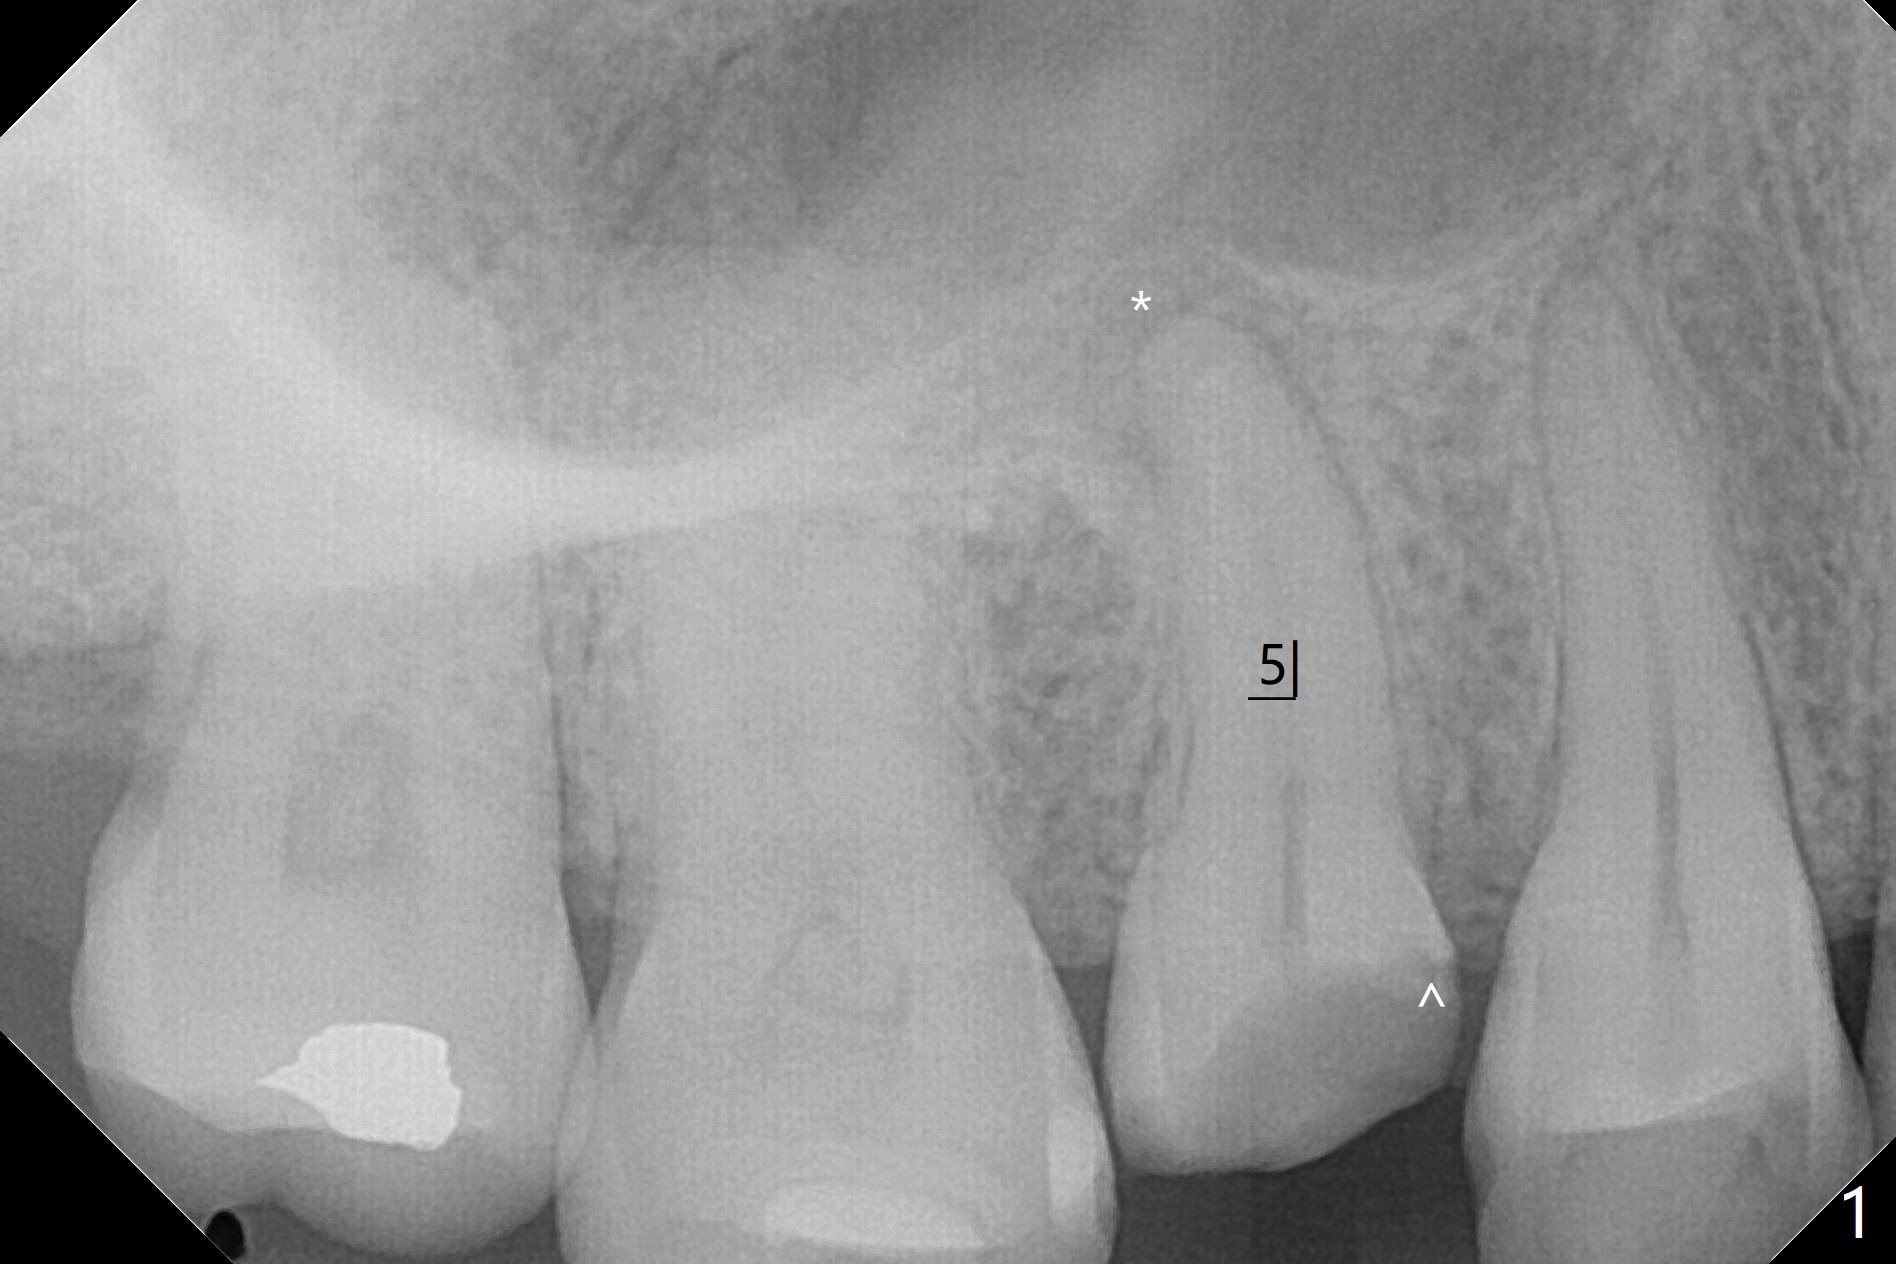

40岁女右上5树脂脱落,少许龋齿,近中边缘稍微龈下(图一:^),轻微叩痛(*)。经过商讨,她选择拔除植牙。CT检查显示上颌窦膜增厚(图二:*),为了减少术后上颌窦炎,第一,Z Pack(上呼吸道广谱抗菌素)和Medrol Dose Pack(激素)处方已开;第二,拔牙后(图三),将PRF膜推入上颌窦(图四:橘黄色),然后粘性骨块(红色圆圈);第三,植体长度刚好穿过窦底板(图五:11.5毫米)。Return to No Deviation 手术 No Neighboring Caries No Antibiotic 8, 10,30/31,19 Armaments 提升 Xin Wei, DDS, PhD, MS 1st edition 10/02/2020, last revision 03/28/2021